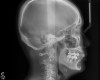

Fig 6. Cephalometric film before treatment.

Figure 6

From radiographic examination, tooth No. 18 was found to have a poor prognosis due to furcation bone loss. The cephalometric x-ray showed a skeletal class II relationship, a reduced mandibular plane angle, flared upper incisors, a deep bite, and significant overjet (Figure 6). The panoramic radiograph confirmed many restorations and that No. 19 was a dental implant (Figure 7). There were no symptoms of temporomandibular joint disorder.